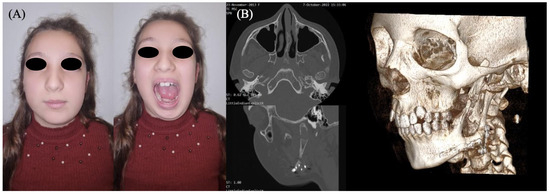

Facelift Approach for Hemimandibulectomy and Costochondral Autologous Graft Reconstruction in a Pediatric Odontogenic Myxoma

Background: Odontogenic myxoma (OM) is a rare, benign, but locally aggressive tumor of odontogenic mesenchymal origin. This study aims to expand current knowledge by integrating a concise literature review with a detailed case report of a surgically complex pediatric OM, treated using a biologically advantageous reconstructive technique. Methods: In this study, we report the case of an eight-year-old girl presenting with a large OM that caused complete disruption of the architecture of the left hemimandible. Due to the tumor’s size and bone involvement, radical resection was necessary. A modified extraoral facelift approach was employed to ensure adequate surgical access while avoiding intraoral incisions and minimizing visible scarring. Immediate mandibular reconstruction was performed using an autologous costochondral graft. Discussion: Although infrequently used in modern surgical practice, the costochondral graft offers unique advantages in pediatric patients due to its inherent growth potential and capacity for long-term biological integration. In this case, the graft allowed restoration of mandibular continuity and form with minimal donor site morbidity, demonstrating its viability even today. Conclusions: This case underlines the importance of tailored reconstructive strategies in pediatric OM. The costochondral graft provided excellent functional and esthetic results, with four-year follow-up confirming stable anatomical remodeling and bone regeneration.